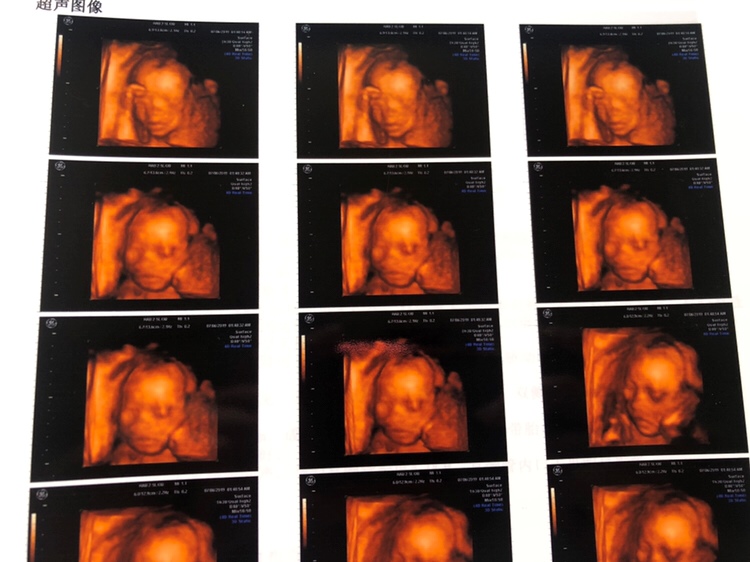

怀孕 孕期产检